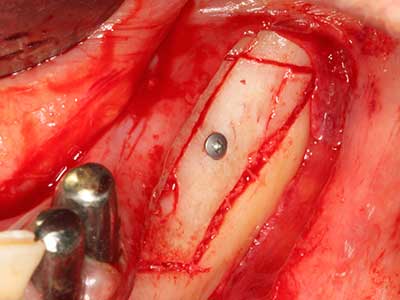

Bei der Knochenblockentnahme zeigen sich weitere Vorteile für die Piezochirurgie: Neben der bereits beschriebenen hohen Präzision bei der Osteotomie stellt sich gerade die Verwendung der dünnen Sägespitzen als besonders materialschonend heraus. Bei der Verwendung insbesondere von Lindemannfräsen sind mit deutlich höheren Entnahmeverlusten durch die dickere Instrumentenspitze zu rechnen (Lakshmiganthan, Gokulanathan et al. 2012). Die insbesondere bei retromolar entnommenen Blocktransplantaten notwendige basale Abtrennung wird durch speziell hierfür vorgesehene rechtwinklige Sägen erleichtert, so dass die Piezochirurgie als präzises, übersichtliches und sicheres Verfahren zur retromolaren Knochenblockgewinnung angesehen wird (Happe 2007) (Abb. 1-12).

Sollen chirurgische Eingriffe mit unmittelbarer Knochenbeziehung an empfindlichen Strukturen wie Blutgefäßen oder Nerven erfolgen, so bergen rotierende Instrumente ein erhebliches Potential an iatrogener Schädigung. Gerade bei Nervdarstellungen nach iatrogener Schädigung, oder aber im Zuge einer Nervlateralisation für resektive und rekonstruktive Eingriffe oder Implantatinsertionen können piezoelektronische Geräte hilfreich sein Knochendeckel zu präparieren und nervnahe Hartgewebsanteile zu entfernen (Abb. 17-20). Ein leichter Kontakt des Nervstrangs zur Piezospitze bleibt dabei in der Regel folgenlos – allerdings kann eine unvorsichtige Vorgehensweise mit sägeartigen Bewegungen bzw. Ansätzen bei noch vorhandener knöcherner Unterlage durchaus temporäre oder aber auch permanente Nervschädigungen verursachen. Das Risiko einer solchen Schädigung wird jedoch als wesentliche geringer eingeschätzt als unter Anwendung von Säge- oder Fräsinstrumenten (Pereira, Gealh et al. 2014).

Wie sich in der Vergangenheit gezeigt hat stellt prinzipiell jeder knochenchirurgische Eingriff eine mögliche Indikation für die Piezochirurgie dar. So lässt sich die Präparation des mobilen Segmentes bei der Distraktionsosteogenese (Abb. 23-25) und der Sandwichosteotomie mit speziellen Ansätzen bewerkstelligen, ohne die für den Erfolg beider Techniken essenzielle Blutversorgung des krestalen Anteils zu gefährden (Gonzalez-Garcia, Diniz-Freitas et al. 2008).

Für die Entnahme von Implantaten ist die Präparation eines vestibulären Knochendeckels möglich, der nach Entfernung der Implantatschraube refixiert wird und auf diesem Wege die Kontur des Alveolarfortsatzes erhält.

Weitere Einsatzgebiete ergeben sich in der Kieferhöhlenchirurgie: Hier können nach konzentrischer Präparation eines in der Regel trapezförmigen Knochendeckels der fazialen Kieferhöhlenwand Pathologien und Fremdkörper aus der Kieferhöhle entfernt werden. Der Knochendeckel wird nach Abschluss des intra-antralen Operationsanteils reponiert und durch Verkeilen oder adaptierende Nähte gegen Dislokation gesichert.